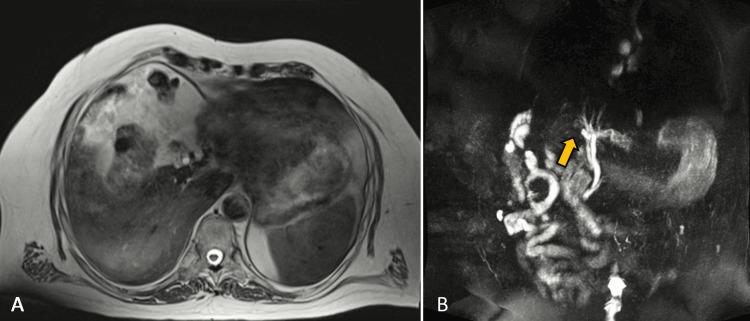

Gallbladder agenesis is a rare congenital malformation that can present itself with comparable symptoms as any case of cholelithiasis. We present a case of a 76-year-old male patient without any medical background of significance who presented at the ER complaining of sudden abdominal pain that started two hours prior to his arrival. Laboratory tests were ordered and an increase in total bilirubin was noted, showing a cholestatic pattern. An abdominal ultrasound was performed where the gallbladder could not be found; therefore, an abdominal CT and an MRI were ordered, which later confirmed gallbladder agenesis. Endoscopic retrograde cholangiopancreatography (ERCP) was then performed with sphincterotomy and the patient was discharged 24 hours later without any complications noted. Gallbladder agenesis is a rare but important diagnosis that general surgeons must have in their diagnostic repertoire because of its ability to mimic acute cholecystitis or cholelithiasis. The objective of this report is to summarize the principal details of this entity.

胆囊缺如是一种罕见的先天性畸形,其表现出的症状可能与任何胆结石病例相似。我们报告一例76岁男性患者,他没有任何重大病史,因突发腹痛前来急诊室就诊,腹痛在他到达前两小时开始。进行了实验室检查,发现总胆红素升高,呈胆汁淤积模式。进行了腹部超声检查,未发现胆囊;因此,又进行了腹部CT和MRI检查,后来证实为胆囊缺如。随后进行了内镜逆行胰胆管造影(ERCP)并实施了括约肌切开术,患者24小时后出院,未发现任何并发症。胆囊缺如是一种罕见但重要的诊断,普通外科医生必须将其纳入诊断范围,因为它能够模拟急性胆囊炎或胆结石。本报告的目的是总结该病症的主要细节。